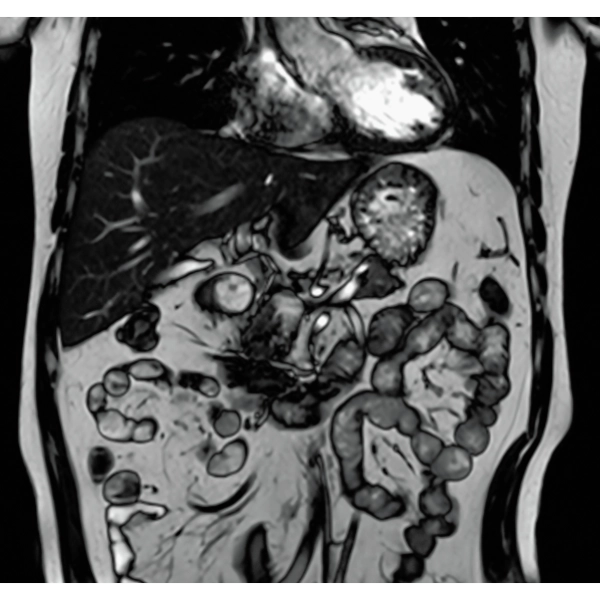

IP-RAPID x DLR Plus can be used for basic imaging such as VolumeScan, RadialScan, HalfScan, and many other imaging methods such as MultiContrastScan FatSep and DWI.

It can also be used with time-consuming scans such as Whole Body DWI and Whole Spine imaging, providing more detailed information in many areas than previously possible.